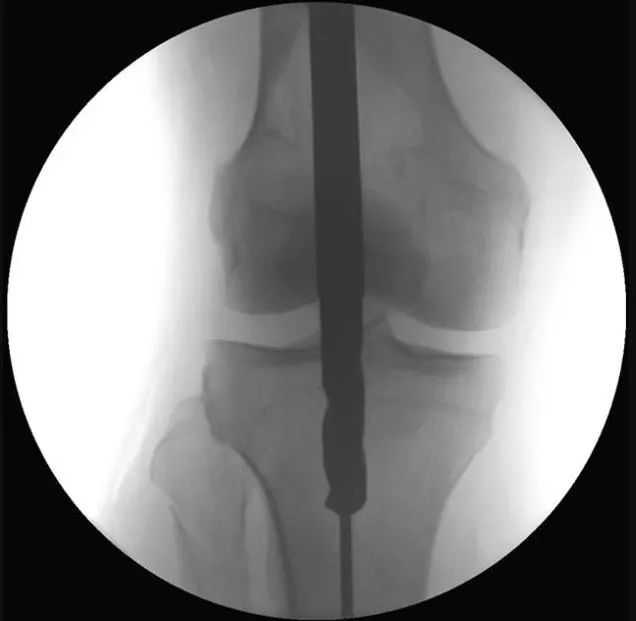

Anu ngabalukarkeun utama malalignment dina fractures tibial proksimal nyaéta deformity disababkeun ku narik tina urat quadriceps salila flexion dengkul jeung konflik mékanis antara ujung kuku jeung cortex tibial posterior salila sisipan susuk. Patella ogé nyegah asupna axial tina paku dina pesawat sagittal (Gbr. 1a, b). Ku alatan éta, métode umum sejen nuliskeun titik ngaliwatan incision parapatellar medial, nu ngakibatkeun sisipan kuku rada medial-to-lateral (Gbr. 1c jeung 2). Nalika kuku asup kana kanal intramedullary distal ka narekahan, bagian proksimal dimiringkeun kana hiji exostosis (Gbr. 2). Tungtungna, tegangan istirahat tina otot chamber anterior nyumbang rada ka ectropion nu (Gbr. 3).

Gambar 1 a,b Ngagunakeun pendekatan infrapatellar konvensional, patella nu nyegah asupna axial tina paku, hasilna deformity umum anterior apical alignment sagittal na ectropion coronal alignment.c Intramedullary alignment kuku dipigawé ngagunakeun pendekatan parapatellar.